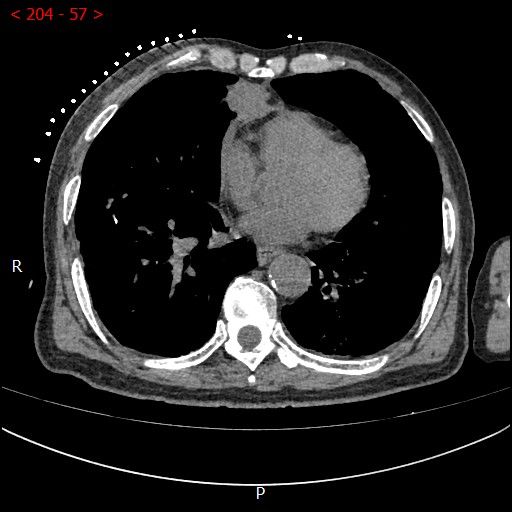

术中影像

男性患者,68岁,检查发现右肺中叶肿块,大小约3.5cm×2.4cm,因患者有慢性支气管炎、肺气肿、肺大泡,基础病较多,无法耐受常规外科手术治疗;经与患者本人及家属多次沟通。血管介入科团队根据患者具体情况决定对该患者施行CT引导下肺肿瘤射频消融术。经全科术前讨论:肿瘤位置毗邻心脏、纵膈、胸膜多处重要器官,手术要求穿刺精准,消融位置精确,尽量避免恶性心率失常,心脏包膜、胸膜、纵膈损伤。经过前期的精心术前准备,2023年7月18日,在血管介入科团队和CT室默契配合下,此次射频消融手术顺利完成。手术全过程仅用时约40分钟,其中消融时间约5分钟。CT观察下见肿瘤形变,周围肺组织呈现“晕”征,提示本次消融范围基本覆盖全肿瘤。术中患者无疼痛并且未产生并发症。本次手术达到杀死肿瘤细胞的同时,最大限度的减少创伤、保留肺组织。